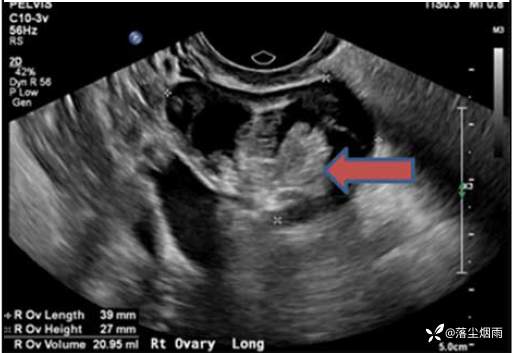

患者血清抗NMDA受体抗体回报阳性。且患者的盆腔超声及MRI提示右侧卵巢肿块,与囊性畸胎瘤表现一致。这些发现确认了抗NMDA受体脑炎的诊断。

图1 盆腔超声发现右侧卵巢肿物,符合囊性畸胎瘤表现